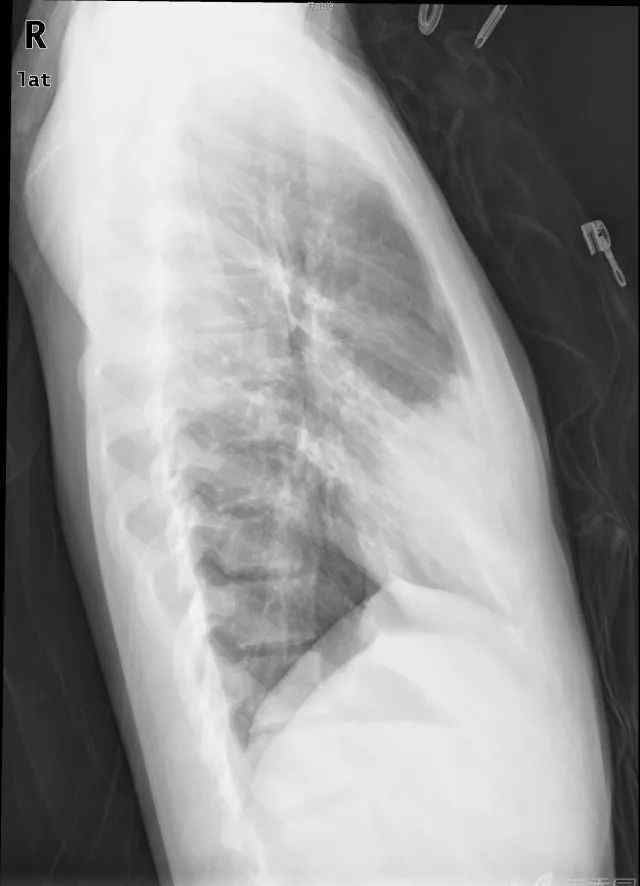

病例2:间歇性咳嗽咳痰1周,伴有发热和右胸痛加重2天

当天照的片子如上,CT左为下图,抗炎6天后CT右为下图。

●侧位片也适用:心脏后缘或左膈后部对应左下叶,右膈前部对应右中叶,右膈后部对应右下叶。

看了轮廓征的解释,病例2的诊断准备出来了吗?右肺中叶大叶性肺炎。